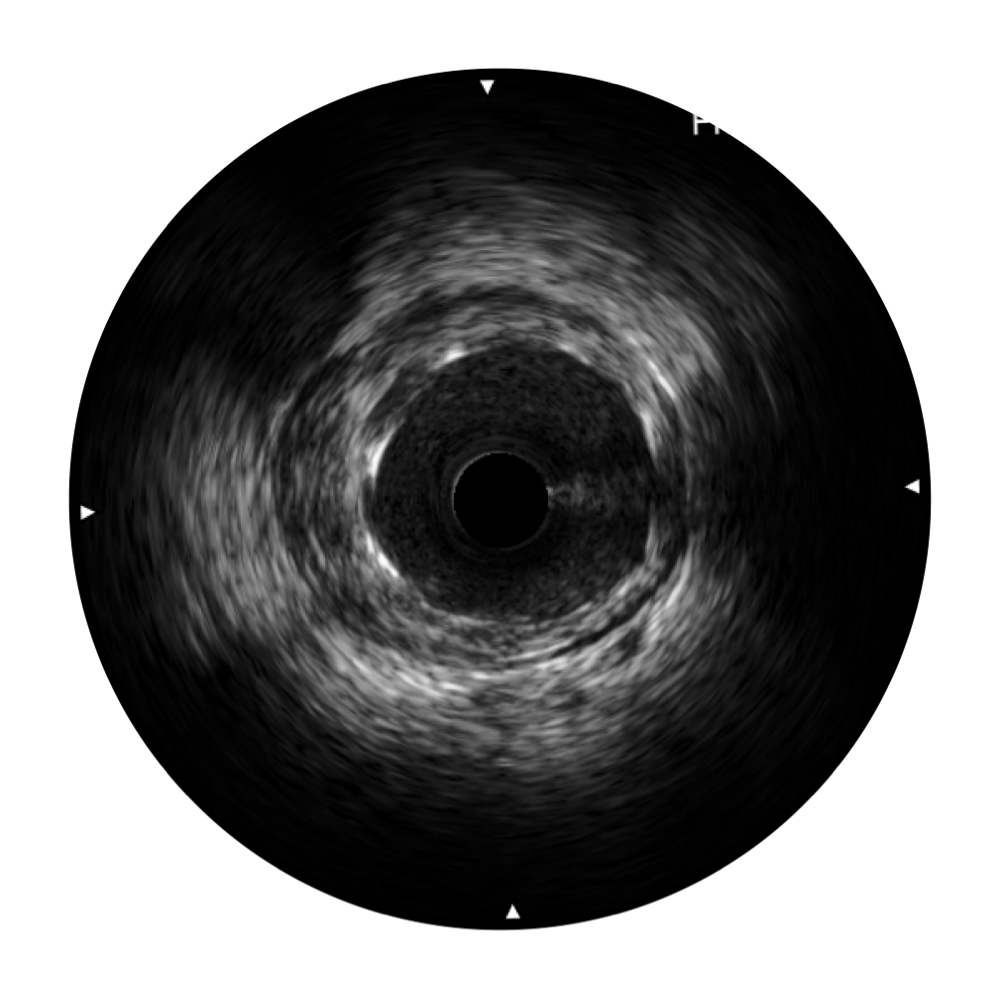

開立寬頻IVUS圖像

傳統(tǒng)IVUS圖像

對(duì)比傳統(tǒng)IVUS導(dǎo)管成像,開立寬頻IVUS圖像的近場(chǎng)支架梁顯影更細(xì)膩,遠(yuǎn)場(chǎng)中膜外血管仍清晰可辨,兼顧遠(yuǎn)中近,兼顧分辨力與穿透深度